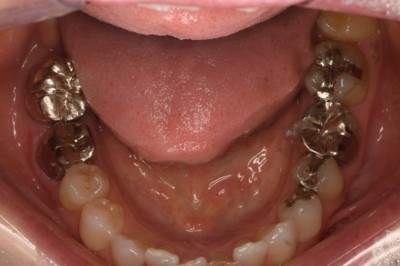

2022.2.5 抜歯後の消毒

口腔内写真

CT画像

骨の状態はそこまで悪くないが、欠損が大きい。

2022.3.12 抜歯1ヶ月後・移植

移植オペ

抜歯をして1ヶ月後、歯ぐきが治ってから、移植をおこなった。

移植時は動揺が大きいため、隣の歯にワイヤーで固定した。

2022.7.9 経過観察後

2022.8.13 クラウンセット

2022.10.16 予後経過

1年後 2023.3 予後経過

レントゲン写真

移植した歯はしっかり機能しており、問題なく使用できているとのことである。